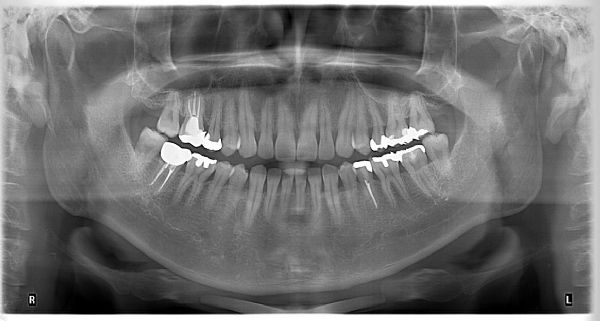

Dijital panoramik röntgen: Sadece lokal bir bölge değil, alt ve üst çenede tüm bölgeler görüntülenebilir. Dijital görüntülemede hastanın maruz kaldığı radyasyon miktarı konvansiyonel cihazlara göre çok azdır. Görüntü dijital ortamda bilgisayara aktarılır ve orada saklanır. Ağız içi kamera: Hasta ağızındaki tüm dolguların, diş taşlarının, çürüklerin, eski kron ve köprülerin, hareketli protezlerin ekranda görüntülenmesini sağlar, tedavi kararının verilmesine yardımcı olur.